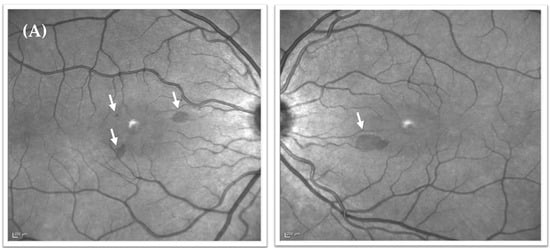

Figure 1.

Near-infrared reflectance images from February 2020, and SD-OCT images from February 2020, December 2020, and March 2021. (A) Near-infrared reflectance images taken at presentation (February 2020) showing three discrete hyporeflective perifoveal lesions in the right eye and one in the left eye (white arrows). (B) Sequence over time of corresponding SD-OCT images through the two larger lesions in the right eye (i,ii) and the lesion in the left eye (iii), initially showing hyperreflectivity in the ONL and OPL with loss of clarity in the outer retinal bands (white arrows). This hyperreflectivity is seen to resolve over a 13-month period accompanied by improvement in the clarity of the outer retinal band architecture.

Despite being overlooked at the time, the near-infrared reflectance image from February 2020 did, in fact, demonstrate three discrete perifoveal hyporeflective lesions in the right eye and one in the left (Figure 1A), with SD-OCT scans demonstrating hyperreflective bands in the outer nuclear (ONL) and outer plexiform layer (OPL) and additional loss of clarity of the outer retinal bands (Figure 1B). These lesions corresponded to the lesions seen on clinical examination in December, and to the negative scotomata the patient had been reporting. The lesions highlighted on near-infrared reflectance had become significantly less prominent over the preceding 10 months (Figure 3). Based on the clinical findings, and in keeping with the history and patient demographics, a diagnosis of acute macular neuroretinopathy was made. The patient was reviewed again in March 2021, at which time symptoms persisted but were less prominent. The lesions seen on near-infrared reflectance were continuing to resolve, but ONL/OPL hyperreflectivity persisted on SD-OCT although this was progressively less prominent on the December 2020 and March 2021 scans, with some improvement also seen in the outer retinal band configuration (Figure 1B).